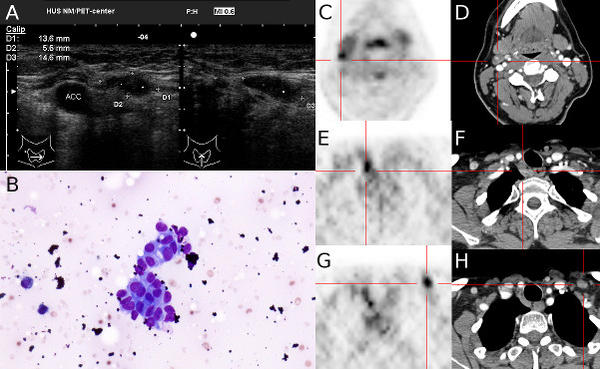

Photo: Biermann et al., Acta radiologica 2015 (with permission).